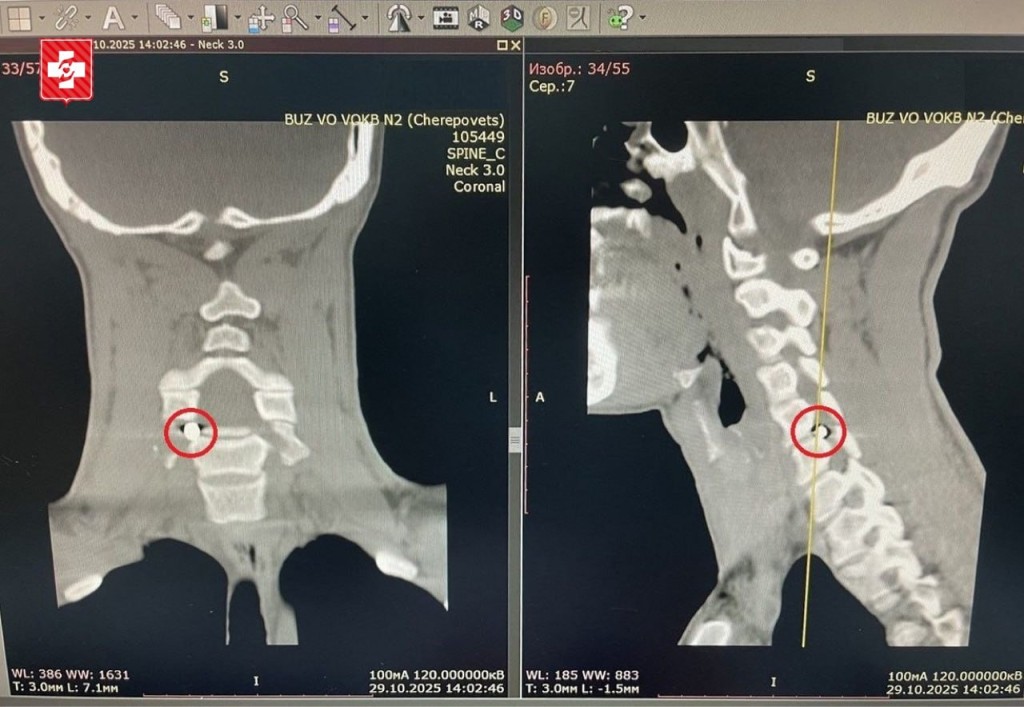

Спиральная компьютерная томография показала в шейном отделе позвоночника металлический фрагмент размером всего 5х4 мм, застрявший прямо в позвоночном канале. Этот осколок давил на спинномозговой корешок, из-за чего любое движение — даже во сне — вызывало резкую боль, иррадиацию в руку, онемение и слабость в кисти.

Особые риски были связаны с расположением осколка рядом с позвоночной артерией. В других клиниках браться за операцию не решились. Однако специалисты нейрохирургического отделения ВОКБ2 приняли пациента и провели гибридное вмешательство с участием рентген-хирургов.